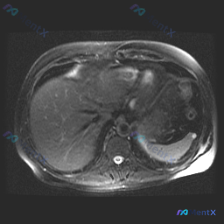

整理了一份挺有警示意义的影像读片资料,不是复杂疑难病,但背后的思维陷阱很值得聊聊。 --- 先看本次的核心影像资料 - 序列: 腹部MRI-T2加权像(轴位,单帧) - 影像客观表现: 1. 肝脏: 实质信号均匀,肝内脉管清晰,无扩张,无局灶性高/低信号灶,包膜光滑 2. 脾脏: 形态正常,实质信号...

最近看到一份读片资料,提问是“观察脾脏病变”,但仔细看完影像和分析后,觉得这个病例的思维转折比诊断本身更有价值,整理一下思路和大家分享。 --- 先看核心影像事实(基于MRI-T2轴位) 这份图像的基本信息很明确:上腹部轴位T2加权像,有轻度呼吸伪影但不影响评估。 直接说关键的阳性/阴性发现: ✅...

看到一个很有意思的影像读片场景,整理一下思路分享给大家。 用户的问题很明确:“这张图能看到什么?脾脏病变。”这直接给了我们一个预设锚点——先入为主地认为“一定有病变”。但按流程看完影像后,结论可能恰恰相反。 --- 一、先看这张T2轴位片的客观所见 我们按解剖结构逐一梳理: 1. 肝脏:实质信号均匀...